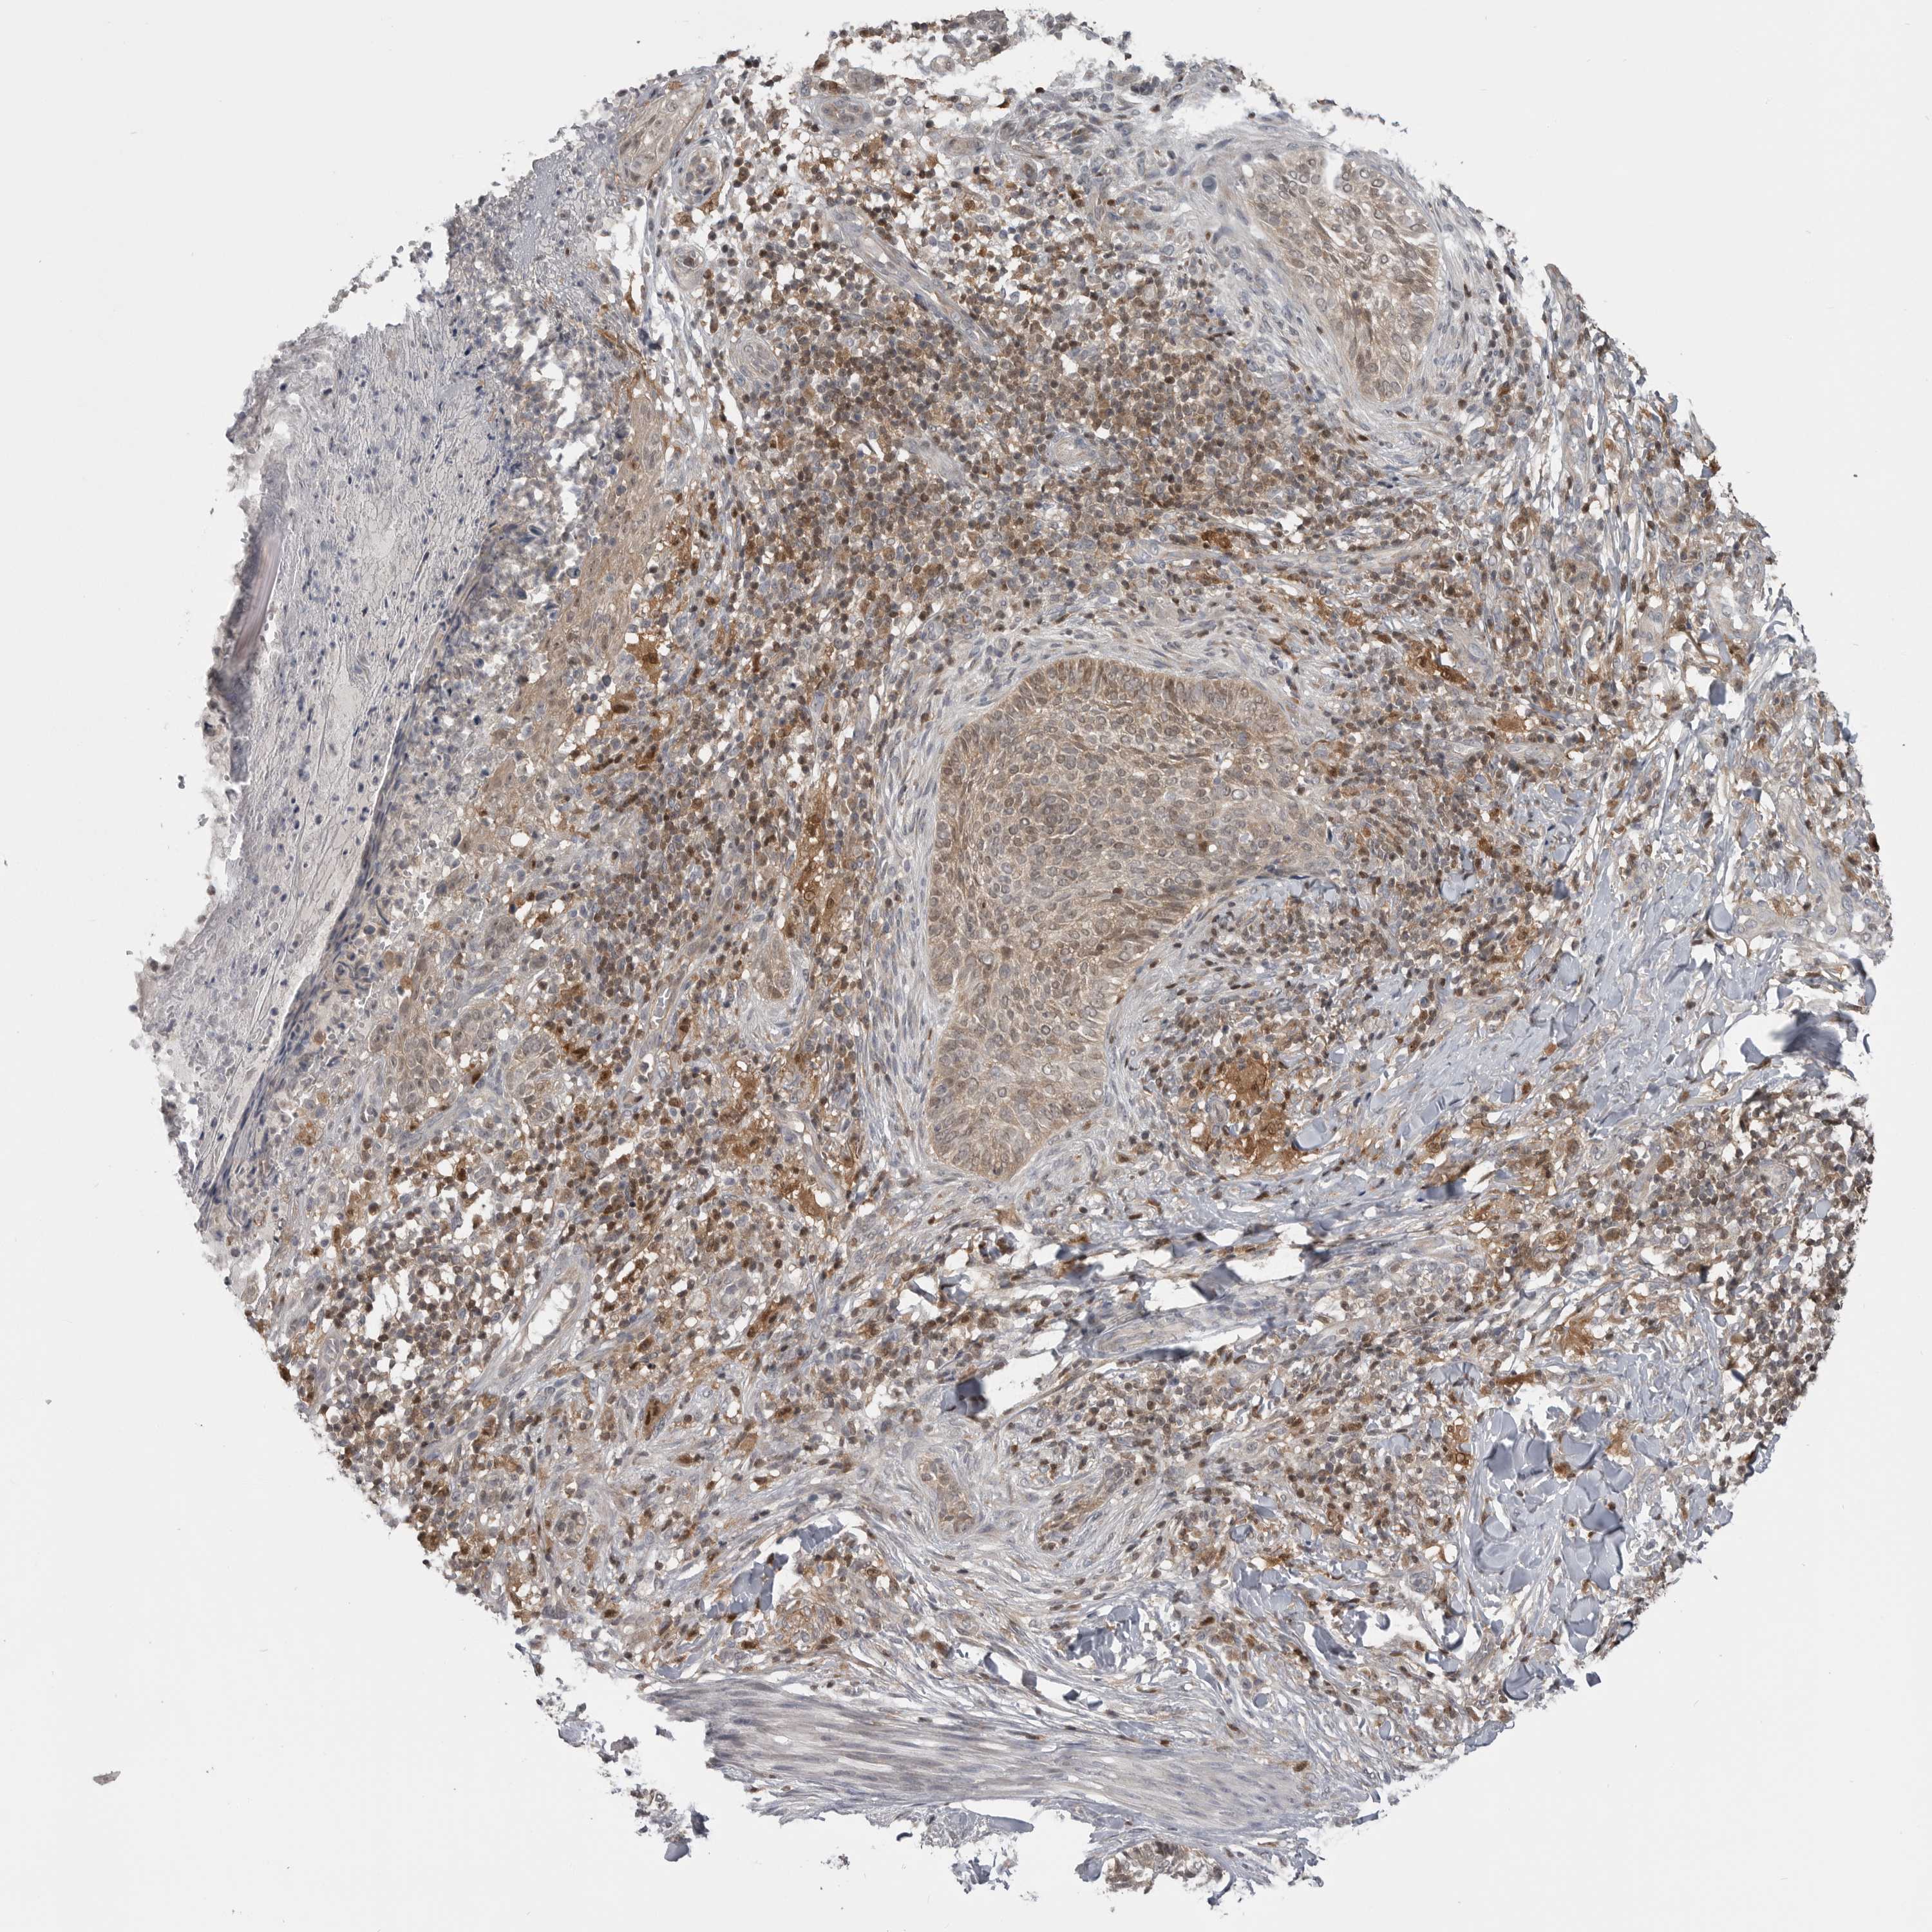

CANCER SKIN CANCER Show tissue menu

SKIN CANCER - Protein expressioni

A mouse-over function shows sample information and annotation data. Click on an image to view it in a full screen mode. Samples can be filtered based on level of antibody staining by selecting one or several of the following categories: high, medium, low and not detected. The assay and annotation is described here.

Each image is clickable and will lead to virtual microscopy that enables deeper exploration of all samples and also displays staining intensity scores, fraction scores and subcellular localization as well as patient and tissue information for each sample.

Antibody HPA007667

Squamous cell carcinoma, NOS

Squamous cell carcinoma, metastatic, NOS